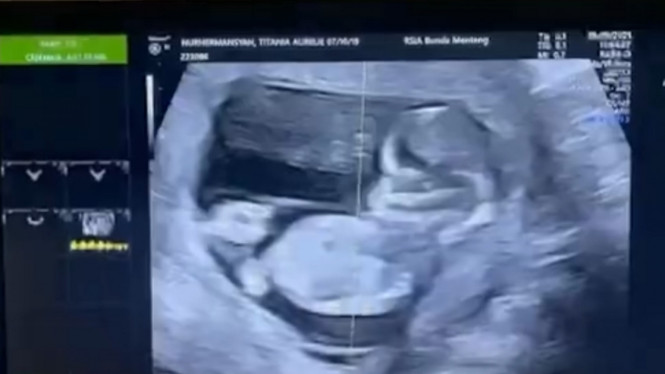

Lewat akun Instagram, Atta Halilintar memamerkan video hasil USG kehamilan Aurel Hermansyah. Dia memeriksakan kandungan sang istri di RSIA Bunda, Menteng, Jakarta Pusat. Terlihat pula pada layar tersebut nama lengkap sang istri, Titania Aurelie Hermansyah.

"Anakku alhamdulilah, Allahuakbar sehat kuat ya anakku, Papa sama mama akan jaga kamu sekuat kami," tulis Atta Halilintar penuh bahagia.